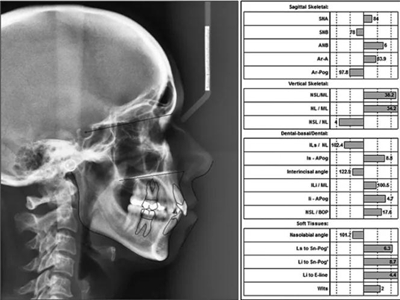

頭影測(cè)量分析,SNA角84°,ANB角6°,高角型,詳見(jiàn)下表。

患者側(cè)貌改善,下唇唇肌緊張消失,上下唇可自然閉合。磨牙及尖牙關(guān)系糾正至I類(lèi),覆合覆蓋正常。上下頜弓型糾正至卵圓形,牙弓寬度增加。頭影測(cè)量分析示SNA角81.8°,ANB角3°。頭影測(cè)量重疊圖示下頜骨向后旋轉(zhuǎn),垂直面高度略有增加。